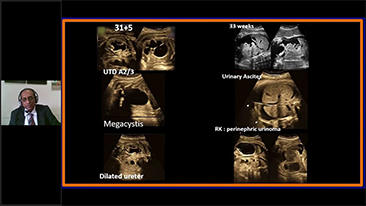

Kad?n sa?l??? tarama ziyaretlerinde yĂŒksek dĂŒzeyde hasta hacimlerini desteklemek i?in, optimize edilmi? OBG i? ak??lar? gerekir. ?rne?in, merkezi sinir sistemi (CNS) malformasyonlar?, en yayg?n g?rĂŒlen konjenital anormalliklerden biridir. K?tĂŒ fetĂŒs pozisyonu gibi, ?e?itli g?rĂŒntĂŒleme durumlar? nedeniyle, 2 boyutlu ultrasonda MSPâyi elde etmek ?zellikle zordur. Bu nedenle, otomatik alg?lama ve ?l?ĂŒmler, tarama verimlili?ini bĂŒyĂŒk ?l?ĂŒde art?rabilir.